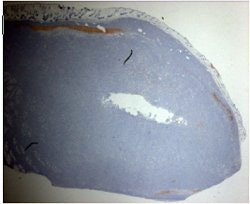

Above, ultrasound image of NHL xenograft done on a 20-MHz transducer at 24 hours after CHOP chemotherapy. The apoptotic areas correspond to the areas of high-intensity backscatter. Below, corresponding histology image with TUNEL stain. The areas that are stained brown correspond to the apoptotic areas. Images courtesy of Dr. Charles Cho.

The animals were then imaged with 20-MHz spectroscopic ultrasound (VS40B, VisualSonics, Toronto). For the 26 mice that had chemotherapy, imaging was done several times, five to 72 hours after treatment. For the eight mice that had radiotherapy, sonography was performed once, six hours after treatment. Tumor sections were terminal transferase dUTP nick end labeling (TUNEL) stained to confirmed apoptotic cell death.

The authors found a time-dependent increase in backscatter following CHOP chemotherapy, they wrote in their results. The measured high-intensity (10-decibel increase) patch areas on ultrasound were 1.76 mm² at five hours, 0.27 mm² at 12 hours, 2.03 mm² at 24 hours, 2.93 mm² at 48 hours, and 0.12 mm² at 72 hours.

"Image analysis demonstrated a correlation between the size of high-intensity patches on high-frequency ultrasound and immunohistochemical TUNEL staining or apoptotic areas," the group wrote.